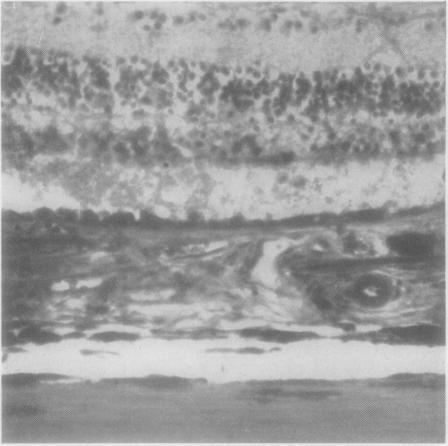

Fundus dystrophy with unusual features; a histological study.

Br J Ophthalmol. 1951 Dec;35(12):751-64. doi: 10.1136/bjo.35.12.751.